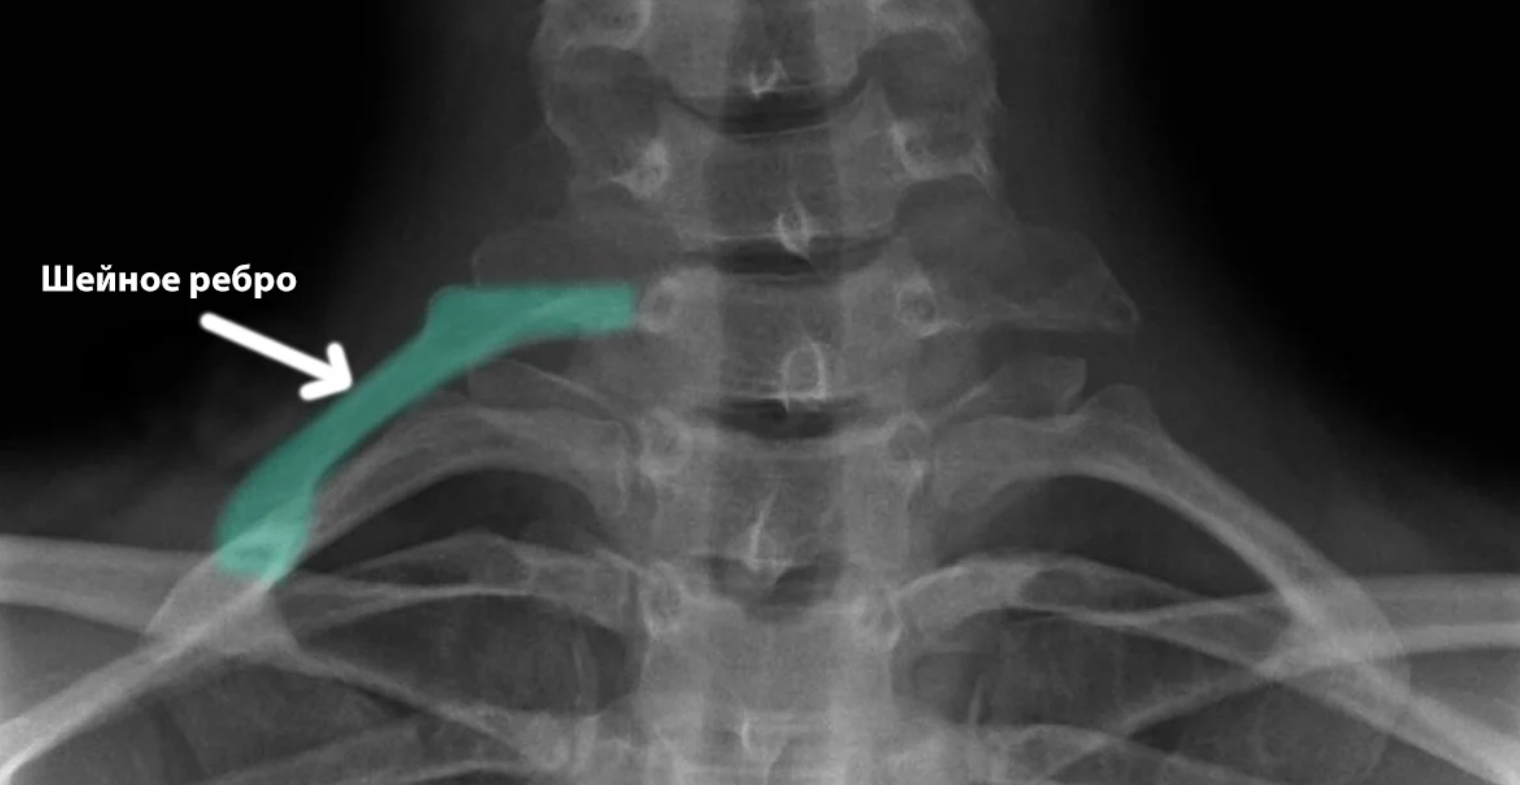

Підключичний м'яз та шийні ребра

Менше 1% має "зайві" шийні ребра, що дісталися від рептилій.

Ознакою еволюційних процесів є і підключичний м'яз - цей невеликий м'яз розташований між першою парою ребер та ключицями.

М'яз потрібен тваринам, що переміщаються на четвереньках. При розвитку прямоходіння потреба в ній у людини відпала, але збереглася на пам'ять про предків.